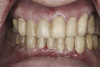

(13.) Preoperative anterior, close-up view.

Figure 13